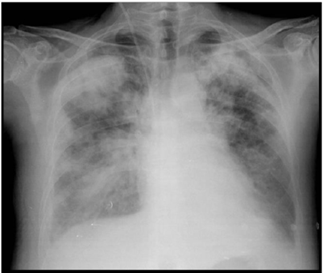

Radiografía de tórax portátil (fig. 1): decúbito con mala penetración, no infiltrados ni derrame pleural. Senos costofrénicos libres.

Respiratorio: sospecha de neumonía por Neumococo; se logró extubar sin incidencias, aunque progresivamente presentó empeoramiento radiológico, sin alteraciones del intercambio gaseoso.

A las 72 horas, por tanto, salió a planta de Neurología para continuar cuidados y a las tres horas de estar en planta se encontró taquipneico, con tiraje y trabajo respiratorio y desaturación brusca, tos y expectoración verdosa. Se observó llamativo empeoramiento radiológico (fig. 2) y se trasladó de nuevo a la Unidad de Cuidados Intensivos por necesidad de intubación orotraqueal.